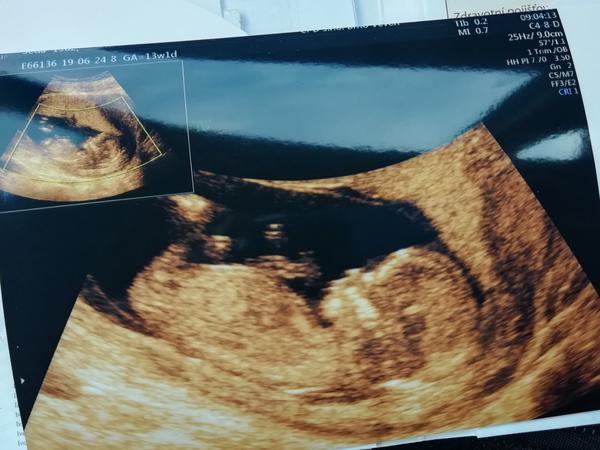

Ahoj devcata,dekuju za podporu,tak dnes bylo vse na jednicku, mimis se mrskal,srdicko blikalo...ja.tomu moc.neverila,tak mi vse dr.ukazovala,kde jsou obaly,kolik ma plodovky,rucky,nozky a tak...takze snad 2.7. Prukazka a nabery a 12.7.genetika...kdyz dojdu az tam,pak se zacnu konecne trochu radovat...❤❤❤a ted uz muzu konecne teda balit a dnes smer Italie😉

Ahoj holky, tak já už mám úspěšně po.. Miminko má 6,1cm a podle Už jsem 12+1tt🙂 Akorát při hlášení anamnezu se doktorce něco nezdálo, takže jdu příští pondělí mimo screeningu ještě i na genetiku.. Tak mám obavu :(